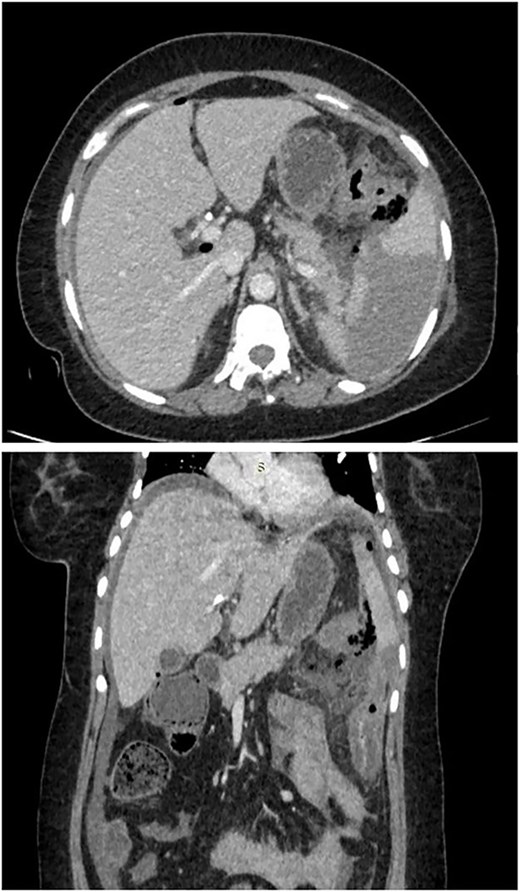

As shown in Fig. 1, computed tomography (CT) scan of abdomen showed pneumoperitoneum in inter bowel space, pancreatic necrosis, peripancreatic collection in splenic flexure region with multiple air foci within it and adjacent mesenteric fat stranding and heterogeneity. (? Splenic flexure of Colon perforation).

CT scan of abdomen showed pneumoperitoneum in inter bowel space, pancreatic necrosis, peripancreatic collection in splenic flexure region with multiple air foci within it and adjacent mesenteric fat stranding and heterogeneity. (? Splenic flexure of colon perforation).